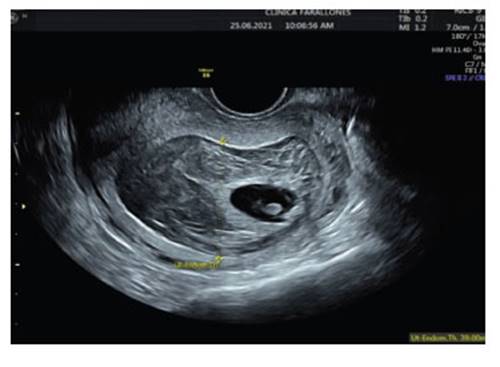

Patient 31 years old, G4 P2 A1, with two vaginal deliveries; the abortion occurred 2 years ago was managed with uterine curettage. Last menstrual period was on May 8, 2021; the planning method consisted of monthly injectable hormonal contraceptive injections (norethisterone (50 mg) and estradiol (5 mg)). She consulted a tertiary clinic for abnormal uterine bleeding. On first admission, incomplete abortion was diagnosed by ultrasound and positive β−hCG; the ultrasound showed a uterus with endometrium of 21 mm, heterogeneous, thickened, with mixed echoes and no other abnormal findings (Figure 1). She underwent curettage with Novak curette, with apparently normal discharge.

On second admission three days later, she continued with vaginal bleeding. Transvaginal ultrasound was reported with uterus in retroversoflexion (RVF), 39 mm thickened endometrium showing echo-mixed content and irregular gestational sac of 22 mm, for 6.6 weeks' gestation containing embryo and vitelline vesicle (Figure 2). A new uterine curettage was performed and the discharge was apparently normal.

Figure 2 thickened endometrium, with ecomixed content and irregular gestational sac of 22 mm at 6.6 weeks' gestation.